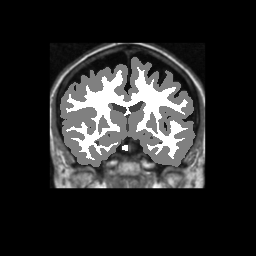

Accuracy is reported as Dice overlaps between a tool's segmentation and the Internet Brain Segmentation Repository (IBSR) manual segmentation for each of the 18 IBSR subjects. The inter-tool comparison (on the left below) shows the median Dice coefficient for each tissue class. The overlaps for FSL (from which the median values are drawn) are shown in the plot on the right.

Overlap coefficients for each tissue class are shown here for each IBSR subject. Select a subject below to see the FSL results compared to other tools.